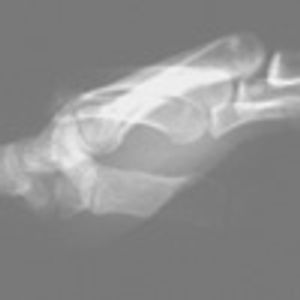

Several hours after striking his closed fist against the side pillar of a passenger car, a 28-year-old man presented with acute pain and swelling of the left hand. The dorsum of the left hand appeared deformed and edematous; there were scattered abrasions but no lacerations, exposed bony fragments, ecchymosis, or active bleeding.